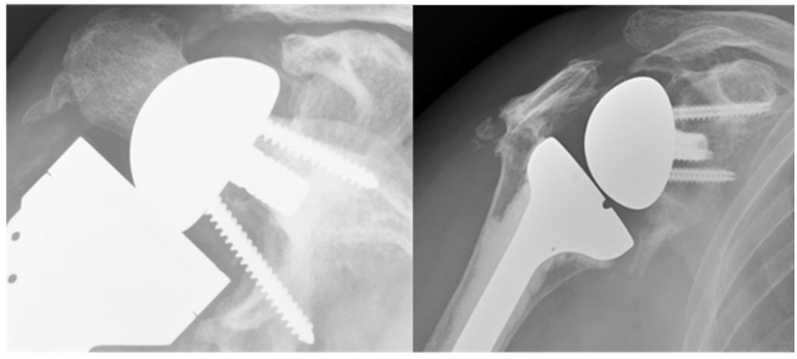

由于创伤性损伤、炎症性关节炎、缺血性坏死、退行性关节疾病的发生率上升以及高要求运动和职业活动的增加,55岁以下患者越来越多地使用肩关节置换术。解剖性肩关节置换术(ASA)仍然是年轻患者的首选手术选择,这些患者的肩袖完整,肩胛盂畸形最小,保留了自然的生物力学,力量和活动范围,并且显示出10-15年的高长期植入存活率。尽管预后良好,但ASA存在潜在的长期风险,包括植入物磨损、假体松动、关节盂糜烂和进行性肩袖退变,尤其是对体力活动的年轻患者。反向肩关节置换术(RSA)在复杂的临床情况下提供了一个有价值的替代方案,其特征是不可修复的肩袖撕裂,广泛的盂骨丢失,严重的解剖破坏或先前的手术失败。对于原发性骨关节炎和完整的肩袖患者,RSA可作为ASR的替代方案,在60岁以上的患者中具有良好的临床效果和生存率。RSA也被成功地用于55岁以下的患者,并取得了良好的短期效果。RSA在年轻、活跃的个体中的寿命和可靠性仍然值得关注。ASA可以修改为RSA,临床效果良好,而RSA失败是极具挑战性的。如果我们接受ASA会随着时间的推移而失效,那么主ASA应该允许对RSA进行轻松修订。模块化假肢设计的最新进展促进了从ASA到RSA的更简单的修订。

Shoulder arthroplasty is increasingly utilised among patients under 55 years of age due to rising incidences of traumatic injuries, inflammatory arthritis, avascular necrosis, degenerative joint diseases and heightened participation in demanding sports and occupational activities. Anatomic shoulder arthroplasty (ASA) remains the preferred surgical option for younger patients with intact rotator cuffs and minimal glenoid deformities, preserving natural biomechanics, strength and range of motion, and demonstrating high long-term implant survival rates at 10-15 years. Despite favourable outcomes, ASA carries potential long-term risks including implant wear, prosthetic loosening, glenoid erosion and progressive rotator cuff degeneration, particularly relevant for physically active younger patients. Reverse shoulder arthroplasty (RSA) offers a valuable alternative in complex clinical scenarios characterised by irreparable rotator cuff tears, extensive glenoid bone loss, severe anatomical disruption or previous surgical failures. RSA can be used as an alternative to ASR for primary osteoarthritis and an intact rotator cuff, with excellent clinical outcomes and survivorship in patients over 60. RSA is also being used successfully in patients under the age of 55 with excellent short-term results. There remain concerns regarding the longevity and reliability of RSA in younger, highly active individuals. ASA can be revised to RSA with good clinical outcomes, while failure of RSA is extremely challenging to address. If we accept that ASA will fail with time, then the primary ASA should allow for ease of revision to an RSA. Recent advances in modular prosthetic designs facilitate simpler revisions from ASA to RSA.